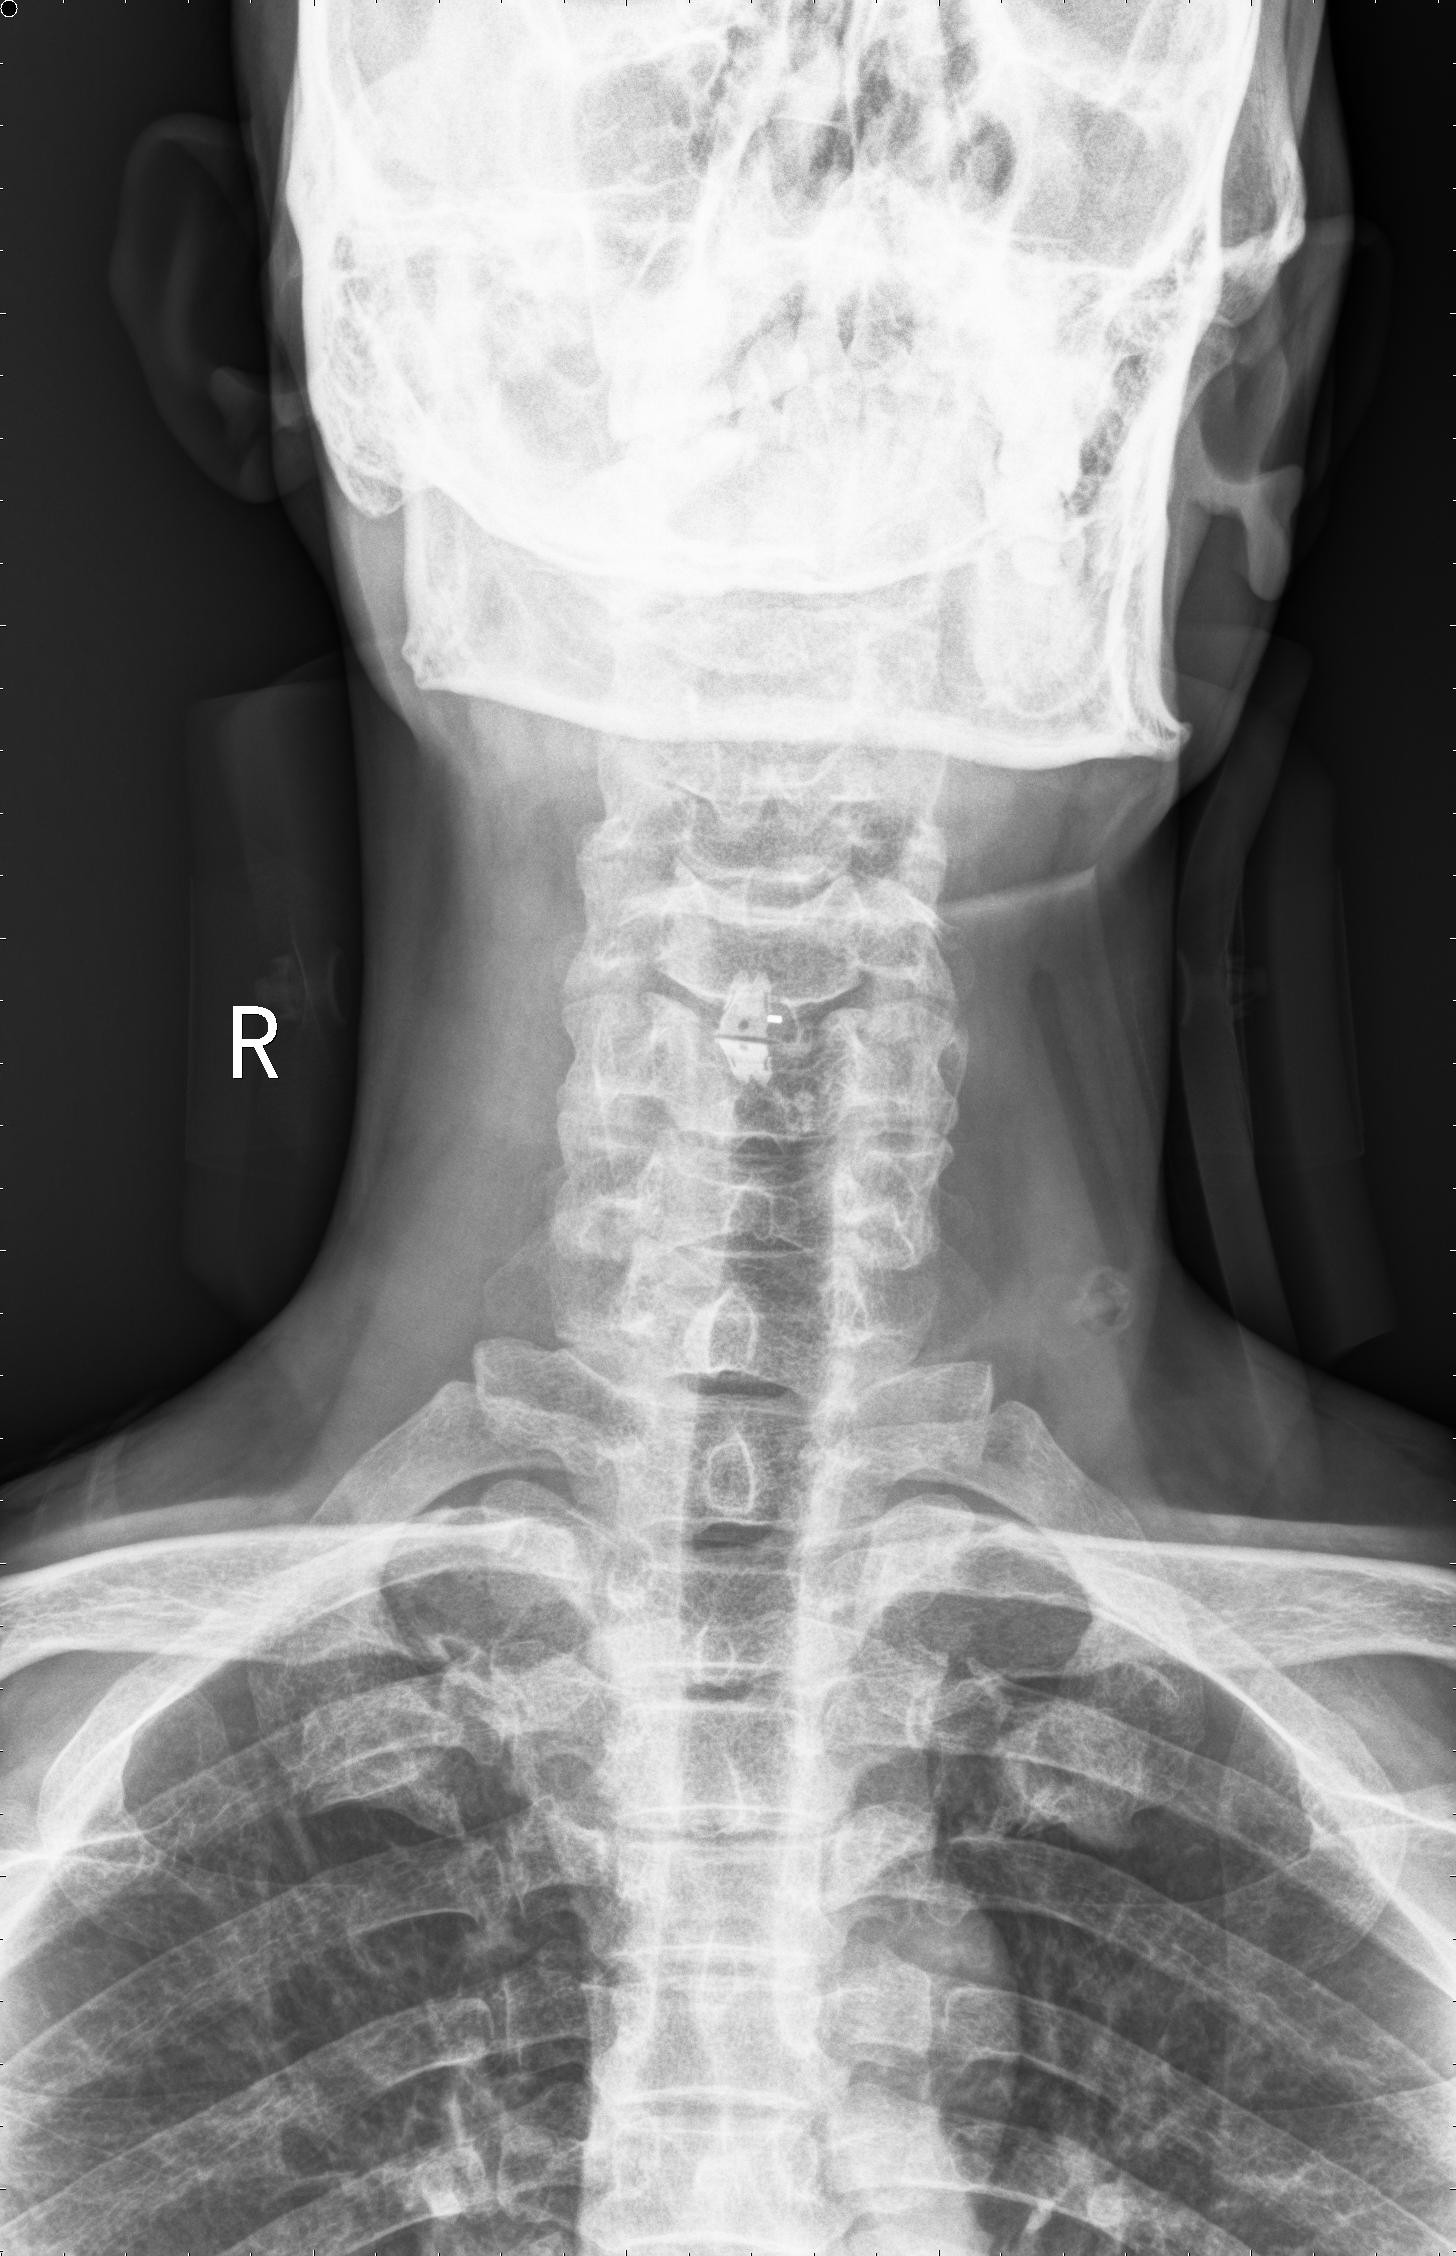

中年男性41歲,因“行走不便2年,加重伴雙手麻木2周”之主訴入院,癥狀主要為:頸部疼痛、僵硬,雙下肢無力、行走不穩(wěn),雙手麻木,協(xié)調性差,右手握筆困難。入院查體:步態(tài)不穩(wěn),C3-C7壓痛、叩擊痛,肢痛溫覺減退,雙上肢肢肌力5-級,雙下肢肌力4-級,肌張力增高,雙下肢腱反射亢進,病理征(+),行頸前路小切口突出椎間盤切除、前路頸椎橋形鎖定植骨融合(ROI-C假體),無需前路鋼板,術后四肢麻木明顯緩解,右上肢精細動作明確增強,可寫字,行走不穩(wěn)消失,肌力基本正常,頸部活動度無明顯受限。(圖1、圖2)

圖2:術后頸椎X線提示頸椎橋形鎖定融合居中,椎間隙高度恢復正常,融合良好。